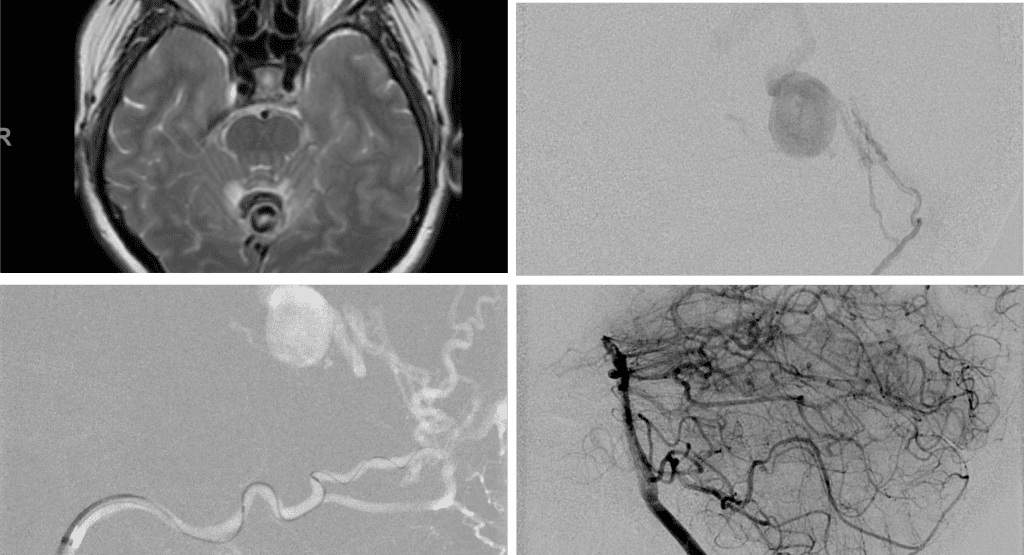

A 55-year-old woman presented with acute onset of severe headache, and possible witnessed seizure. Imaging confirmed intraventricular hemorrhage primarily focused within the fourth ventricle with diffuse subarachnoid hemorrhage within the posterior fossa and along the tentorium as observed on non-contrast CT and MRI of the Brain (Figure 1).

Figure 1. A and B) Non-Contrast CT Axial and Coronal demonstrate large, ruptured Varix/Aneurysm along the Incisura of the posterior fossa which appears to have mixed hemorrhagic components and enhancement on MRI T2 and post contrast imaging (C and D).